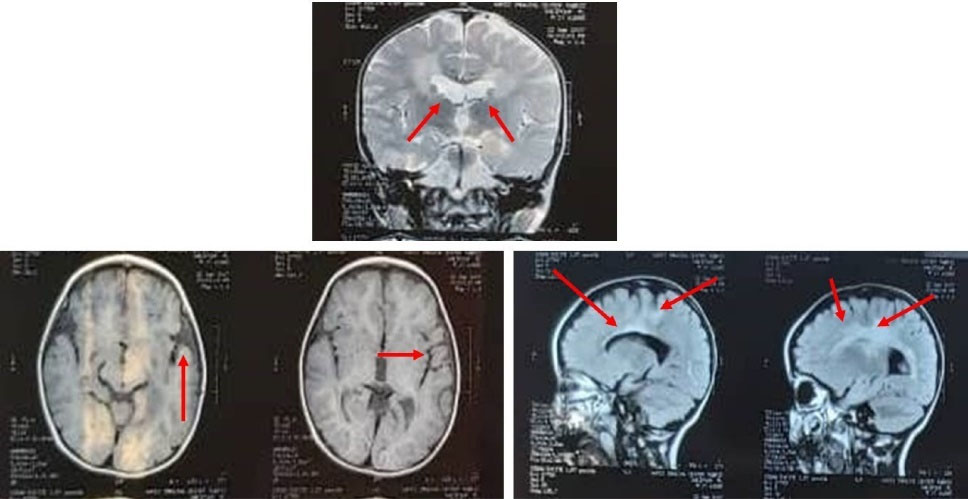

The index patient was a boy, born in 2005 as the first child of healthy consanguineous parents, who referred to Tabriz Genetic Analysis Centre (TGAC) for severe motor dysfunctions, dysphagia, cognitive impairment, and blindness. The patient died at the age of 9 years. The symptoms were initiated with visual problems at one month of age, progressive cognitive decline, gait disturbance, and epileptic seizures above the age of two years. Furthermore, he was admitted several times to the hospital due to shortness of breath and aspiration pneumonia. Magnetic resonance imaging (MRI), and computed tomography (CT) scans were obtained. The brain MRI performed at 2 years of age showed confluent high signal foci at proventricular with matter and subcortical region bilaterally. In addition, mild deep white matter volume loss was evident, and cerebral sulci and ventricles were prominent (Fig. 1). Moreover, the cranial CT scan at 5 years of age revealed a decrease in periventricular white matter with considerable calcification in bilateral basal ganglia, grey-white matter junctions, and cerebellar dentate nucleus. Furthermore, the presence of dilatation of the ventricular system and significant cerebellar hypoplasia with mega cisterna magna were observed (Fig. 2). The family pedigree is depicted in Fig. 3A.

Fig. 2.

MRI findings showing bilateral, and confluente high signal area in the periventricular white matter and subcortical region, plus mild deep matter volume loss, with the prominence of the sulci, and ventricles.

The family under our study, a patient with the aforementioned symptoms was referred to our center with medical documents compatible with leukodystrophy (Figs. 1 and 2). Therefore, due to the heterogeneity of leukodystrophies, we decided to perform a targeted NGS panel in the index patient, his father, his pregnant mother, and the mother's fetus to diagnose the pathogenicity of the disease. We identified a novel homozygous missense variant (c.2498C>T; p.T833M) in exon 19 of the CSF1R gene in our index patient and fetus. Previously, according to the OMIM database, pathogenic mutations in CSF1R just caused HDSL. The father and mother of the patient both were heterozygous for the mutation, and they were 39 and 34 years old, respectively. Therefore, regarding the fact that HDLS is an autosomal dominant adult-onset disease,

In addition to the age of onset of HDLS in our patient and inheritance pattern in his family, we executed additional clinical investigation to reveal the exact cause of the disease. As well as MRI and CT scan outcomes that were more compatible with BANDDOS rather than HDLS, the patient had pectus abnormalities, respiratory problems, aspiration pneumonia, visual problems, and skeletal abnormalities that all confirmed our hypothesis that our patient had BANDDOS. After identifying the cause of the disease, the mother of the patient chose to abort the fetus, who was homozygous for the mutation, after genetic consulting. Following that, performing ovum donation and preimplantation genetic diagnosis, the pregnant woman achieved a normal pregnancy leading to a child who was wild type for the variant. He is now one-year-old and a healthy child.